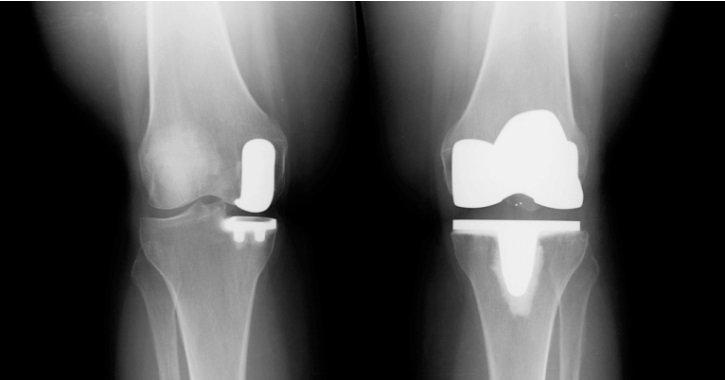

Protezarea parțială a genunchiului, cunoscută drept proteză unicompartimentală este o procedură chirurgicală de înlocuire a unei suprafeței articulare uzate. În același timp, se păstrează toate părțile sănătoase ale cartilajului și toate ligamentele. Comparativ cu o proteză totală, se păstrează aproximativ 80% din structura proprie a articulației.

Conceptul de artroplastie unicamerală presupune înlocuirea doar a părții distruse a articulației, păstrând totodată cât mai mult posibil din ligamente, menisc, cartilaj și os pe cealaltă parte sănătoasă a genunchiului.